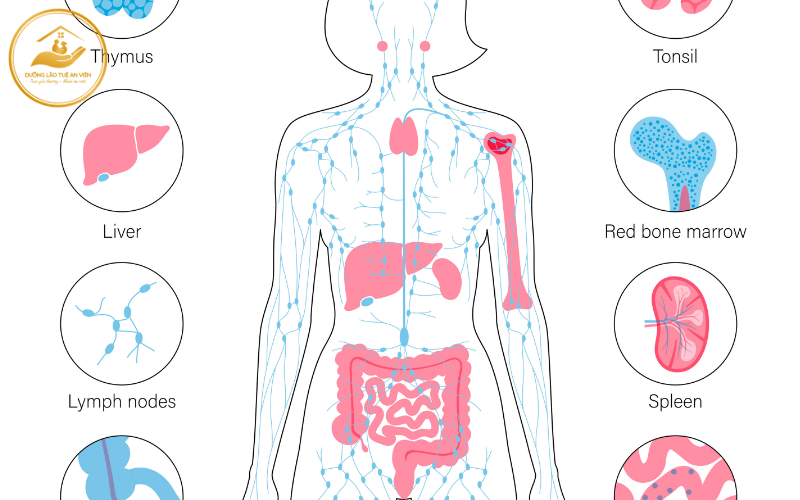

1.4 Hệ miễn dịch suy yếu – tăng nguy cơ biến chứng

Hệ miễn dịch suy giảm theo tuổi tác khiến người cao tuổi dễ mắc bệnh, nhiễm trùng và mệt mỏi kéo dài. Trong quá trình phục hồi chức năng, điều này có thể dẫn đến:

-

Gián đoạn tập luyện

-

Thời gian hồi phục kéo dài

-

Giảm động lực vận động

Lúc này, vai trò của dinh dưỡng trong quá trình phục hồi chức năng còn nằm ở việc tăng cường sức đề kháng, giúp cơ thể chống chọi với bệnh tật và duy trì trạng thái ổn định để tập luyện lâu dài.